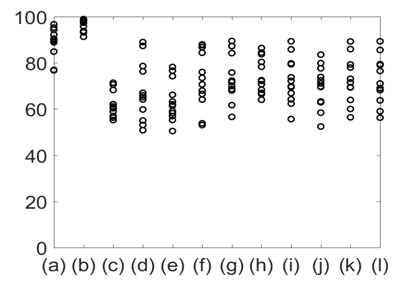

The average respiratory rate was calculated for all the signals of interest and all 12 subjects. This is plotted in Figure 8. The results shown in Figure 8 suggest that the average respiratory rate was 14 with standard error of 4 breath per minute. Subsequent analysis suggested that the overall accuracy in detecting respiratory rate using all modalities varied between 85-100% with GSR having the highest in accuracy (100%). The %Phase match for each test signal for 8 subjects is plotted in Figure 9.

Figure 8 Average respiratory rate with standard error for: (a) Lung volume change; (b) Chest wall movement; (c) GSR; baseline wonder of: (d) SCG-craniocaudal, (e) SCG-lateral, and (f) SCG-dorsoventral; amplitude modulation for: (g) SCG-craniocaudal; (h) SCG-lateral; and (i) SCG-dorsoventral; and frequency modulation for: (j) ECG, (k) SCG-craniocaudal, (l) SCG-lateral, and (m) SCG-dorsoventral signal for all 12 subjects. The average respiration rate was found to be around 14 with a standard error of 4 breath per minute.

Figure 9 %Phase match between the reference signal (lung volume) and other signals. (a) Chest wall movement; (b) GSR; baseline wonder of: (c) SCG-craniocaudal, (d) SCG-lateral, and (e) SCG-dorsoventral; amplitude modulation for: (f) SCG-craniocaudal, (g) SCG-lateral, and (h) SCG-dorsoventral; and frequency modulation for: (i) ECG, (j) SCG-craniocaudal, (k) SCG-lateral, and (l) SCG-dorsoventral signal for all 12 subjects. The phase match with the reference signals was highest for GSR.

Figure 10 shows the mean and standard deviation of %Phase match values of the different physiological signals with respect to lung volume. The results shown in Figures 9 & 10 indicate that the %Phase match values for different test signals varied from about 50% to 98%. The GSR signals showed the highest accuracy in the %Phase match (approximately 94%-98%) for all cases. The chest wall movement and SCG baseline wondering (in the craniocaudal, lateral, and dorsoventral directions) waveform also showed promising results (approximately 85%-94%, 70%-85% ,65%-90%, 65%-85% respectively).